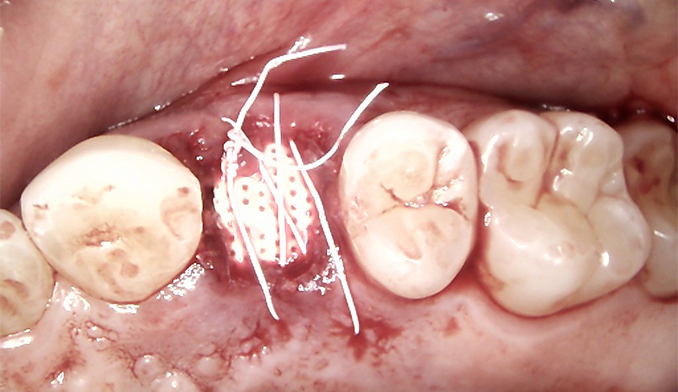

Molar Extraction, Bone Grafting, and Implant Placement

The patient’s lower right molar was severely damaged and could not be saved. After removing the tooth, we performed bone grafting to preserve the bone structure, ensuring a strong foundation for future treatment. Four months later, after proper healing, a dental implant was placed to restore function and maintain jaw health.